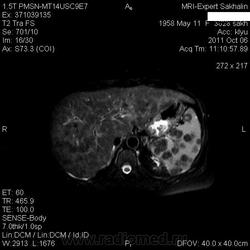

Изменения печени и селезенки.

похоже на метастазы, особенно в селезёнке, с центральным распадом. Хотелось бы и Т1 ВИ увидеть.Чётче на них видны были бы видны очаги в печени и вообще метастазы меланомы например могут иметь усиленный сигнал по Т1. а то в печени как будто множественные гипоинтенсивные очаги с отёком, но не совсем уверен, выглядит как просто пёстрая картинка.

а не лимфома это ? печень мне видится в  виде узлового поражения  и очаговое поражение селезенки.

о лимфоме я подумал в первую очередь, но у семелки вроде узлы всегда хоть немного, но с усиленным сигналом по Т2. и опять же нет лимфоузлов.. вроде.

Метастатическое поражение печени и селезенки, характерно для мелко-клеточного рака легкого.